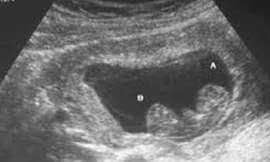

Trước việc một bé gái 14 tuổi đến bệnh viện để sinh con, ban lãnh đạo bệnh viện thấy việc có dấu hiệu “bất thường” nên đã trình báo lên cơ quan chức năng.